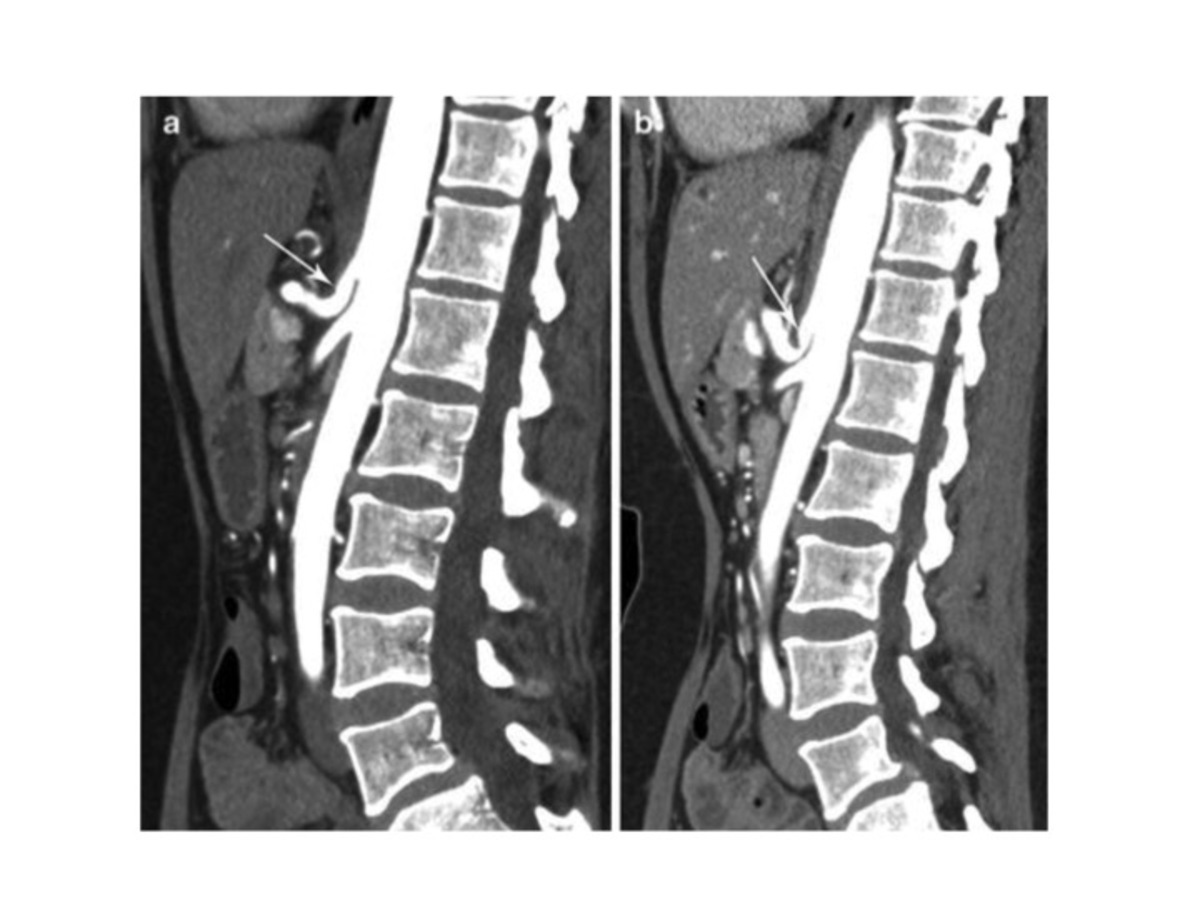

A 68-year-old woman presents with over 4 years of intermittent diffuse lower abdominal pain. She does not have chronic medical problems and relies on acute care clinics and emergency departments for medical needs. She has never undergone colonoscopy. Previous imaging with abdominal ultrasound and CT scan of the abdomen have been negative to date. On exam, she is in moderate to severe distress with diffuse abdominal pain, a distended abdomen, nausea, and obstipation. There is no stool in the rectal vault. She undergoes a CT scan [figure]. What should be done next in this patient’s care?

• This patient has clinical and imaging evidence of entero-enteric intussusception. Intussusception is defined as the invagination of one segment of the bowel into an immediately adjacent segment. The intussusceptum refers to the proximal segment that invaginates into the distal segment, or the intussuscipiens (recipient segment).

• The natural history of intussusception starts with a lead point, typically neoplastic (such as lymphadenopathy, polyp, or cancer), which acts as a focal area of traction that draws the proximal bowel within the peristalsing distal bowel. Symptoms occur due to continued peristaltic contractions of the intussuscepted segment against the obstruction. With continued invagination resulting in edema, eventually the vascular flow to the bowel becomes compromised, resulting in ischemia to the affected segment that can result in necrosis and perforation. In the adult population, intussusception is frequently due to a pathologic lead point, which can be intraluminal, mural, or extramural.

• Classic findings on transverse imaging include the “target sign” or “doughnut sign,” with the presence of several concentric rings of varied echogenicity. On longitudinal imaging, several thin parallel stripes of varying degrees of echogenicity are typically seen, yielding the “pseudokidney sign.” Intussusception has a characteristic appearance on CT that consists of peripheral intussuscipiens and central intussusceptum.

• En bloc resection is generally performed for adult colonic intussusception, and colonic reduction of intussusception is not usually attempted because of the risk of perforation and spillage of microorganisms or malignant cells.